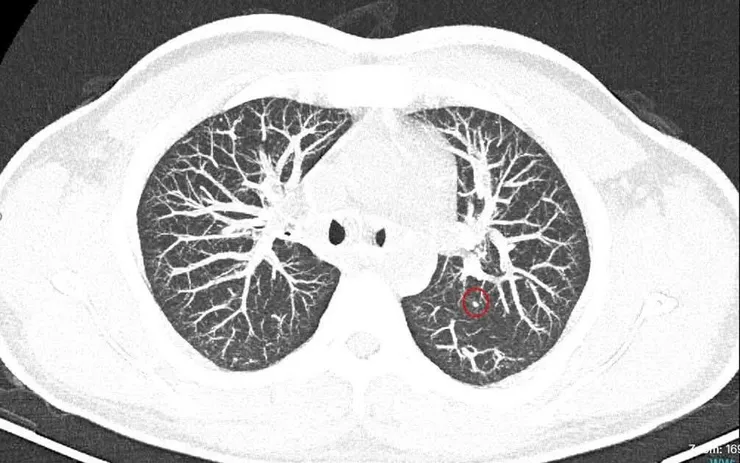

Ngay sau đó, bệnh nhân được chỉ định chụp cắt lớp vi tính (CT) ngực, qua đó phát hiện nhiều nốt tại phổi nghi ngờ tổn thương di căn xa.